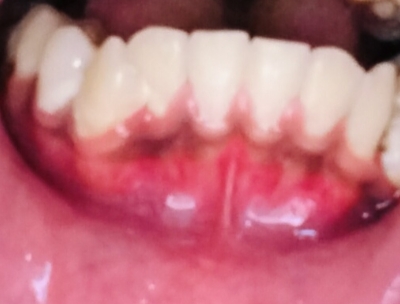

ใครรู้ช่วยบอกที่ครับว่านี่คือเหงือกอักเสบมั่ยแล้วถ้าเป็นมีวิธีแก้ไขยังไงครับใครรูช่วยบอกที่ครับตอนนี้เครียดมากๆกลัวฟันจะหลุด😭

เหงือกอักเสบ

โรคปริทันต์จำแนกตามลักษณะได้ 2 ชนิดคือ โรคเหงือกอักเสบ และโรคปริทันต์อักเสบ #โรคเหงือกอักเสบ โรคที่แสดงภาวะการอักเสบเฉพาะบริเวณเหงือกเท่านั้น สามารถพบได้ในประชากรทุกกลุ่มทุก

โรคเหงือกอักเสบ อันตรายที่เกิดในช่องปาก เหงือกอักเสบ (gingivitis) คือ สภาวะการอักเสบที่เกิดขึ้นกับเนื้อเยื่อช่องปากในส่วนที่เรียกว่าเหงือก โดยมีลักษณะบวม แดง มีเลือดออกง